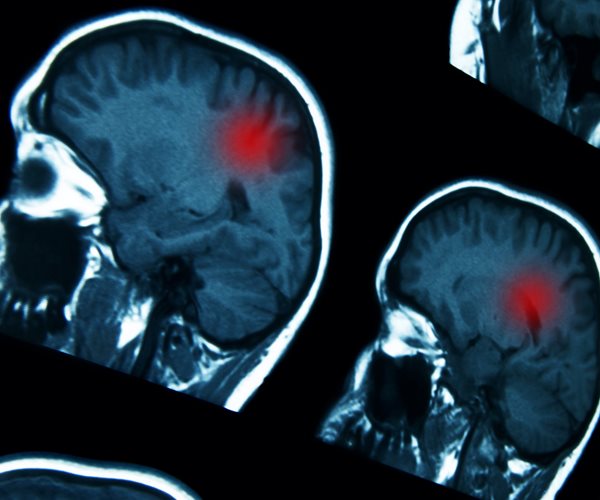

Brain problems linked to even mild virus infections – STUDY

Potentially fatal COVID-19 complications in the brain including delirium, nerve damage and stroke may be more common than initially thought, a team of British-based doctors warned Wednesday.

Severe COVID-19 infections are known to put patients at risk of neurological complications, but research led by University College London suggests serious problems can occur even in individuals with mild cases of the virus.

They found 10 cases of temporary brain dysfunction, 12 cases of brain inflammation, eight strokes and eight cases of nerve damage.

Most of those patients with inflammation were diagnosed with acute disseminated encephalomyelitis (ADEM) — a rare condition typically seen in children after viral infections.

“We identified a higher than expected number of people with neurological conditions such as brain inflammation, which did not always correlate with the severity of respiratory symptoms,” said Michael Zandi, of UCL’s Queen Square Institute of Neurology and University College London Hospitals NHS Foundation Trust.

The research, published in the journal Brain, showed that none of patients diagnosed with neurological problems had COVID-19 in their cerebrospinal fluid, suggesting that the virus did not directly attack their brains.